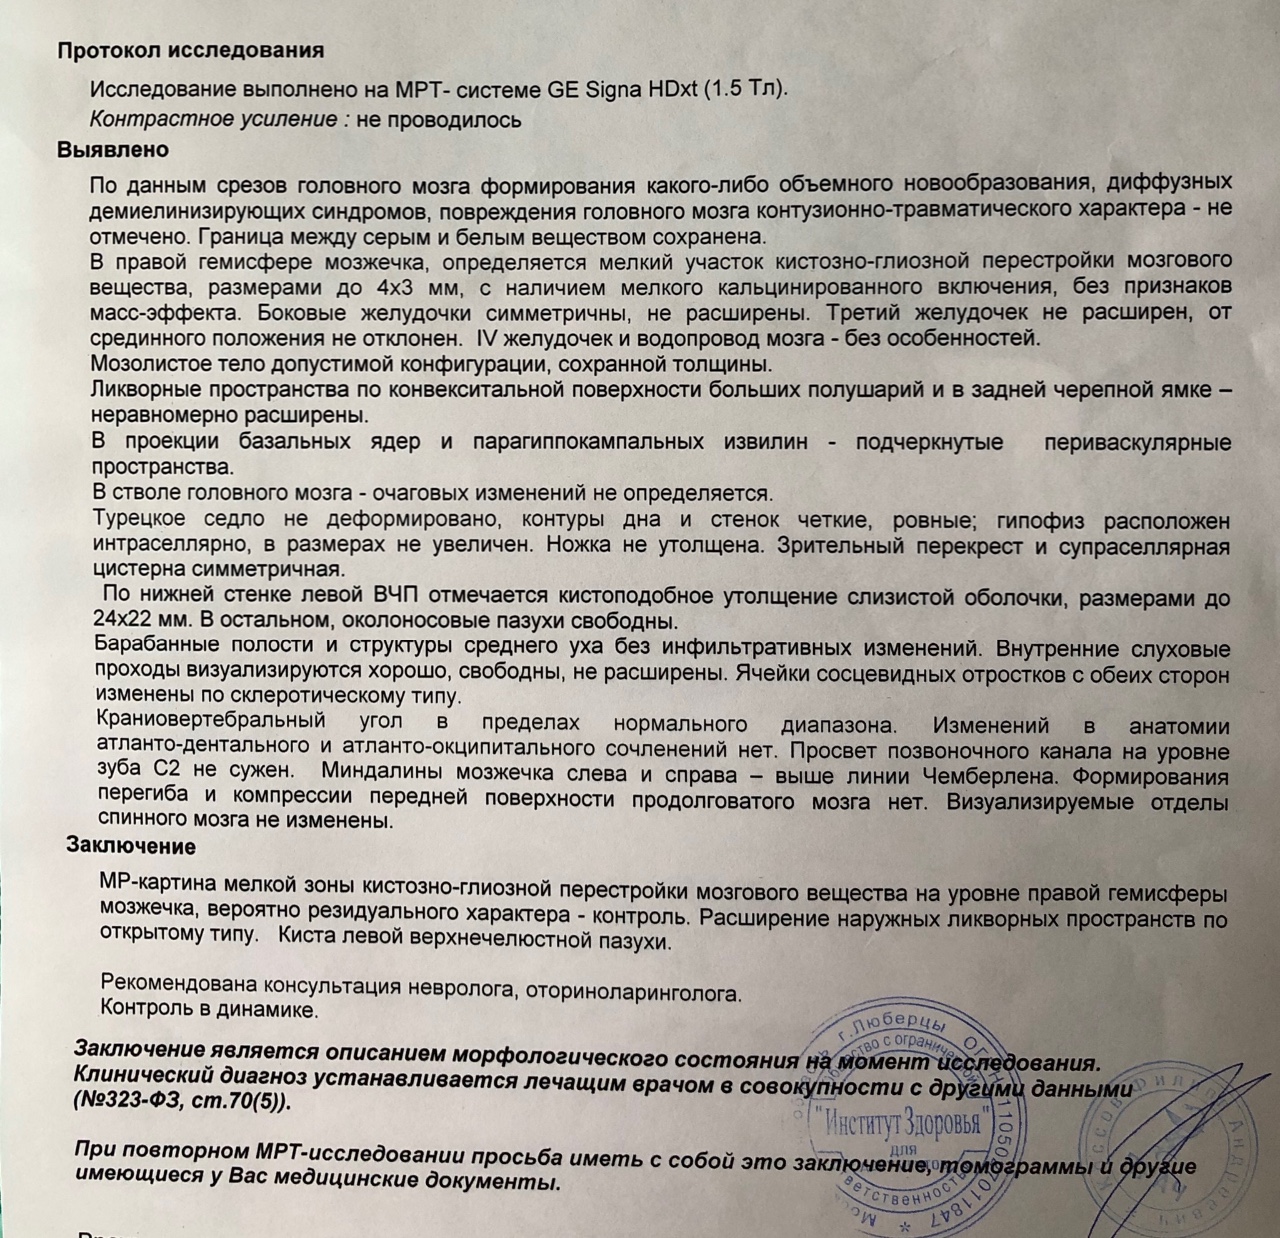

МРТ головного мозга: Расшифровка снимков и Интерпретация

Раздел: Визуальные уроки